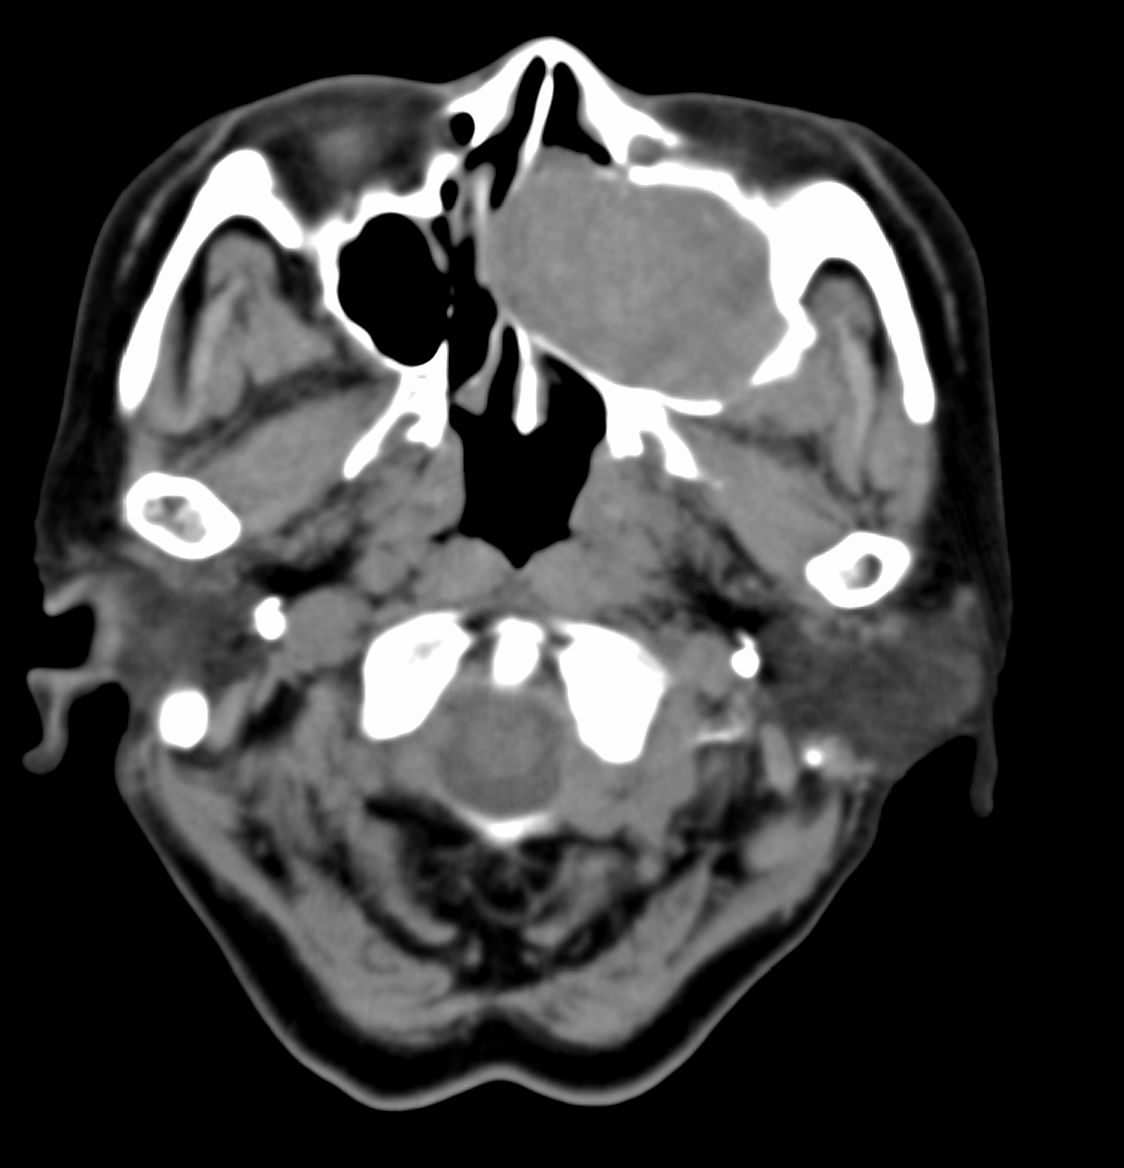

女,69岁。鼻出血2月多。(会诊病史就这样简单)鼻副窦ct检查如下:

左侧鼻腔及上颌窦见软组织块影,左侧上颌窦腔扩大,骨质吸收,右侧上颌窦见半圆形软组织密度影,鼻中隔向右侧弯曲,左侧鼻和鼻窦内翻型乳头状瘤可能性大,建议增强。

左侧上颌窦及鼻腔内见软组织密度影,其内密度不均匀,见斑片状高密度影,右侧上颌窦腔明显扩大,窦壁吸收变薄,鼻中隔右偏,右侧上颌窦见一半圆形软组织密度影,边界清楚,其内密度均匀。诊断,1、左侧鼻腔及上颌窦内翻乳头状瘤可能性大,上颌窦癌,息肉及霉菌性上颌窦炎待除外。2、右侧上颌窦粘膜下囊肿。

1)考虑左侧上颌窦内翻乳突状瘤突入左侧鼻腔。2)副鼻窦炎,右侧上颌窦黏膜下囊肿。

病理:霉菌性左侧上颌窦炎伴左侧上颌窦纤维组织增生。

窦腔密度不均匀增高,无明显钙化征象,后外侧及内侧窦壁膨胀明显,局部破坏消失,筛窦受累及,但双侧对比发现左侧窦壁骨质有硬化增白现象,这可能是支持左侧霉菌性上颌窦炎的主要依据点。